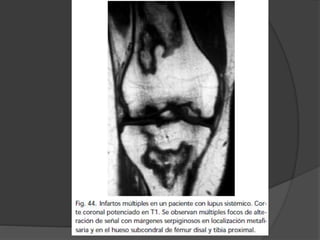

Osteonecrosis  Se instalacuanto el traumatismo produce daño vascular  Causas no traumáticas  Embolización arterial: Hb-patías, descompresión, embolia grasa pancreatitis  Vasculitis : LES  Presión intraósea elevada  Inhibición de la angiogenia (esteroides)  Tensión mecánica  Exposición a radiación